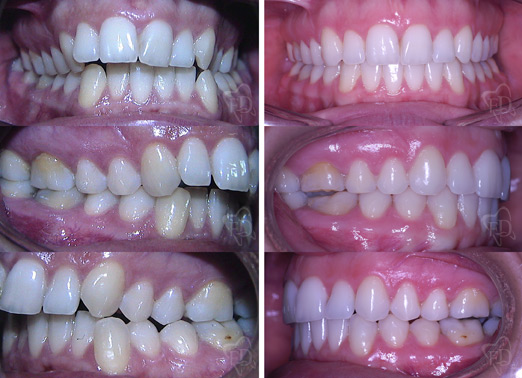

Malocclusione II classe adulto:

prima dopo